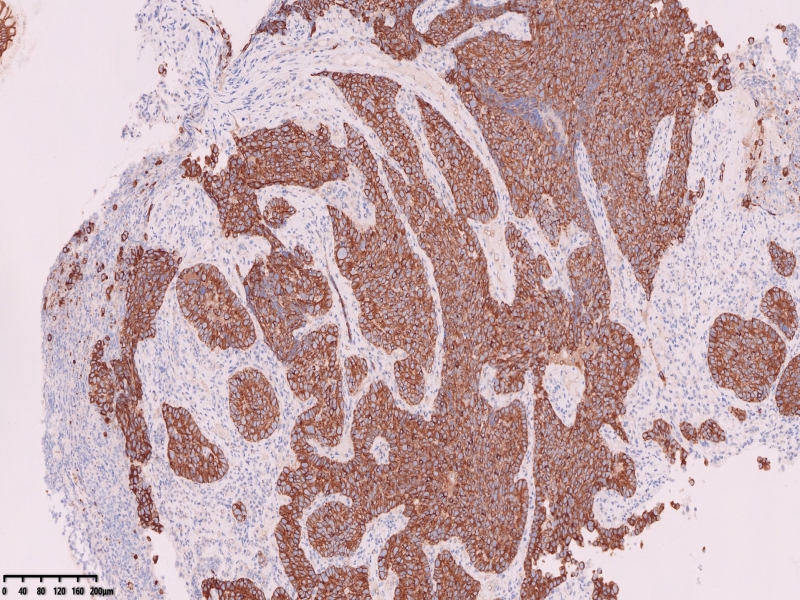

CEA

CA19-9

CAM5.2

P53